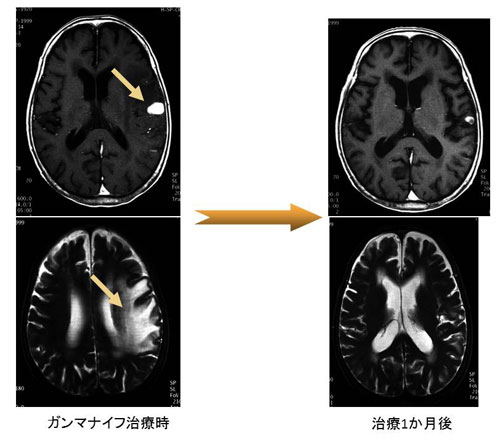

症例1 80歳 大腸がんの左前頭葉への脳転移(図3)

図3左上段のMRIで矢印に示した白く造影されている部分が、大腸がんからの脳転移です。1.5cmくらいの大きさですが、図3左下段のMRIのごとく周囲に強い脳浮腫(雲がかかっているように白く見える部分)があり、右片麻痺と失語症状を認めました。ガンマナイフ治療後、2週間で症状は徐々に回復し、1か月後のMRIでは病巣の縮小ならびに脳浮腫の改善を認め(図3右)、神経症状も完全に回復しました。

図3